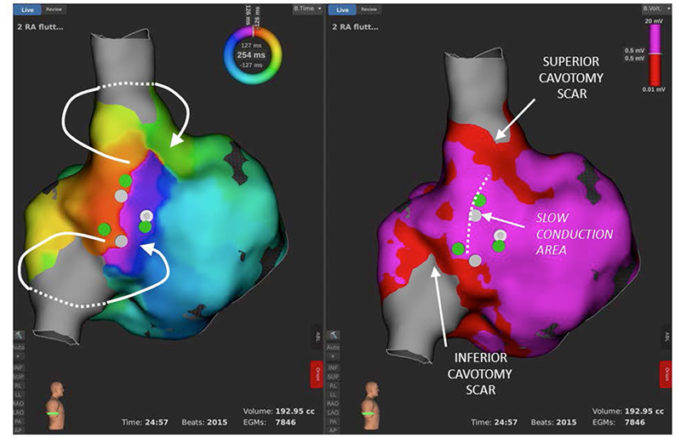

Rhythm AI has announced publication of a human clinical outcome study for its Stochastic Trajectory Analysis of Ranked signals (STAR) mapping system in Circulation: Arrhythmia and Electrophysiology. STAR mapping is designed to improve outcomes in patients receiving ablation treatment...

Sequential approach using STAR mapping system identifies key early sites of activation in patients with persistent AF